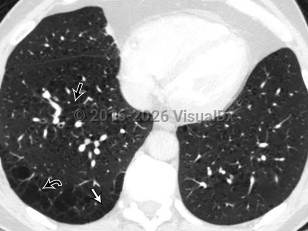

Pulmonary emphysema is a type of chronic obstructive pulmonary disease (COPD) characterized by the loss of individual alveolar wall structures, resulting in larger and less efficient alveoli with air trapping. Shortness of breath begins gradually; it may take years for affected patients to seek treatment. Other findings include wheezing, cough, chest pain, cyanosis, and increased heart rate.

Emphysema is a chronic medical condition. While pharmacologic and lifestyle changes may improve symptoms, in general, patients have a gradual increase in symptoms and burden of disease with time. The primary cause is smoking and/or inhalation of other pollutants. Pulmonary emphysema can also be secondary to alpha-1 antitrypsin deficiency, which leads to unopposed elastase activity in the lung. Treatments include lifestyle changes, supplemental oxygen, medications, and possibly surgery.